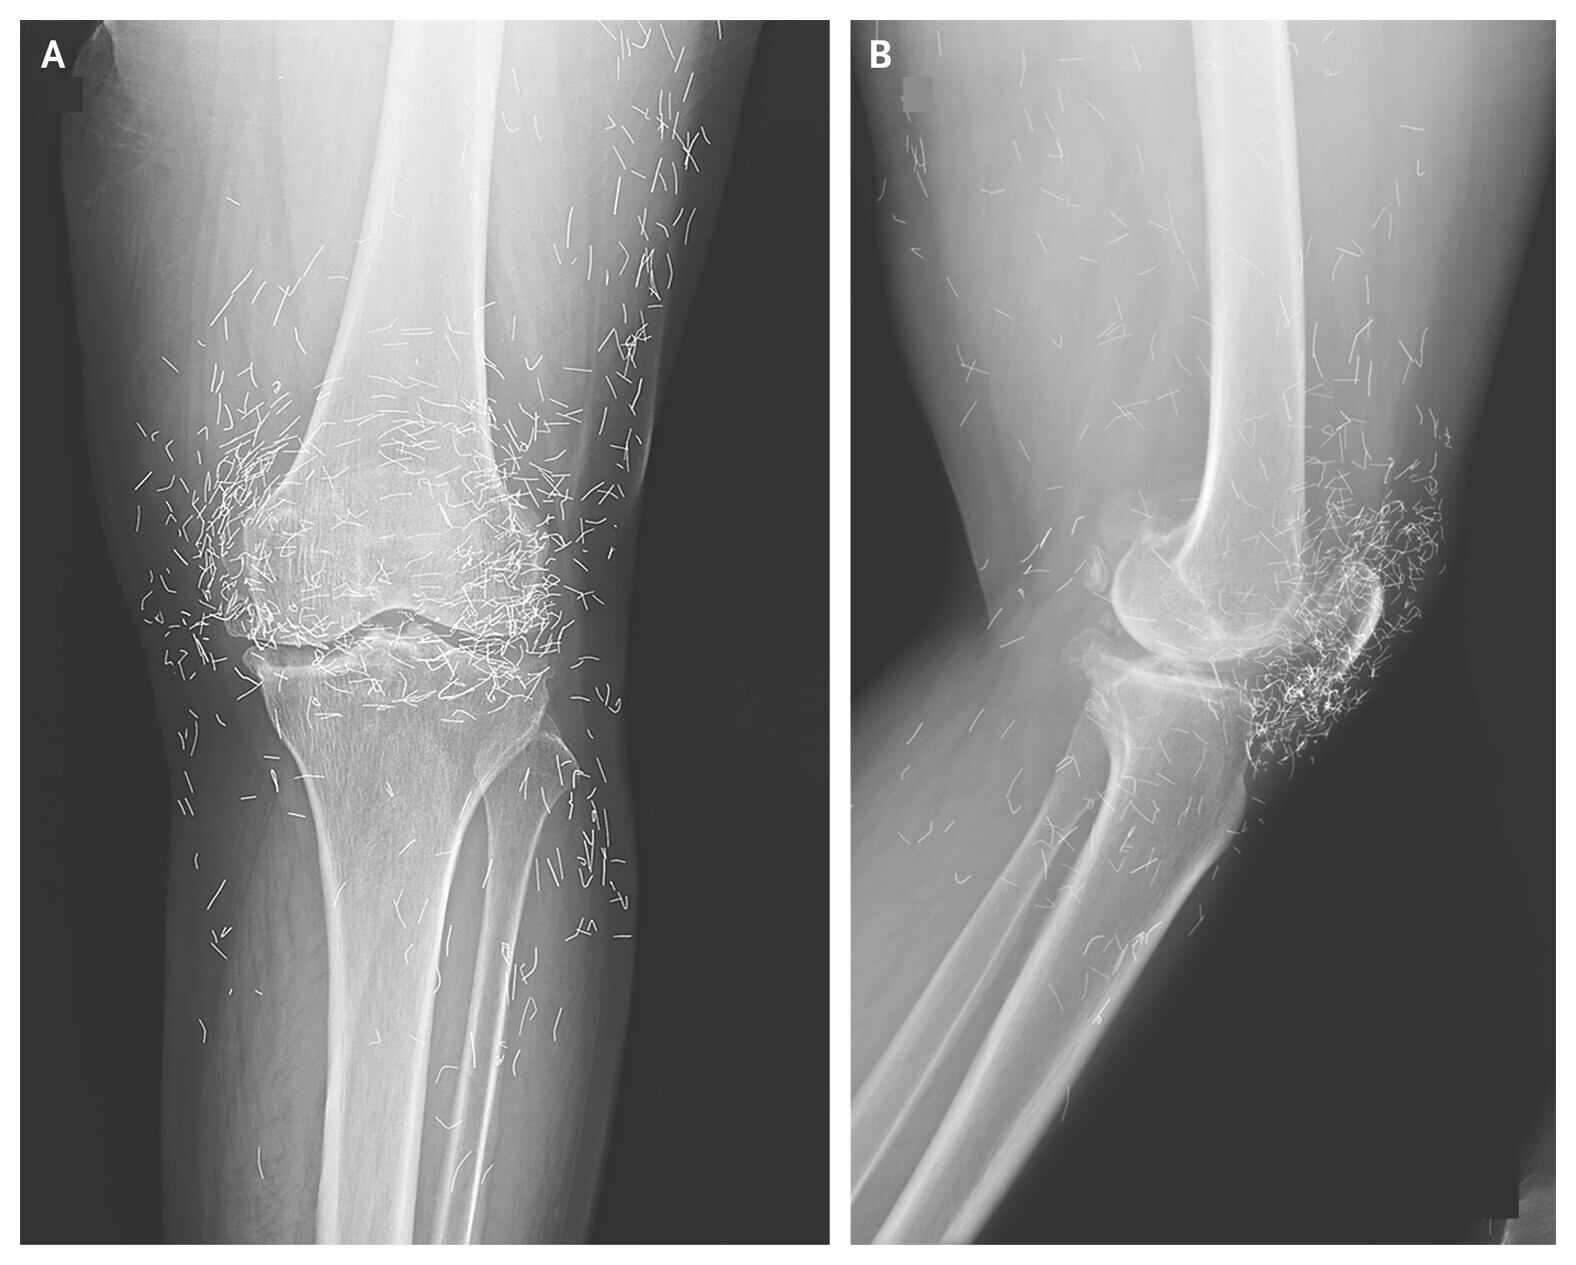

Exames de imagem revelaram alterações no joelho esquerdo. A tíbia, na parte interna da articulação, estava mais espessa e endurecida. Também havia esporões ósseos, que são crescimentos de osso, próximos à região do fêmur e da tíbia. Além disso, os médicos observaram centenas de pequenas manchas ao redor da articulação. Posteriormente, descobriram que eram fios de ouro inseridos em sessões de acupuntura.

O caso do joelho também mostrou que os fios dificultam a interpretação de exames de imagem. Radiografias podem ser prejudicadas, e exames de ressonância magnética ficam contraindicados, já que o movimento do metal pode perfurar tecidos e até danificar artérias.